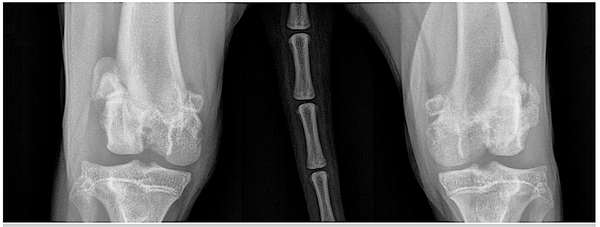

FIGURE 2. Radiographs of a 13-month-old female spayed Labrador retriever diagnosed with bilateral grade IV lateral patellar luxation with no CCL rupture. The patient was treated with bilateral trochlear wedge resections and tibial tuberosity transpositions, followed by physical rehabilitation. (A) Preoperative ventrodorsal view. (B) Preoperative mediolateral view of left hindlimb. (C) Preoperative mediolateral view of right hindlimb. Courtesy of Dr. Beck at Backlund Animal Clinic, Omaha, Nebraska

Diagnosis of PL is primarily based on palpation of the affected stifle. Radiography can help determine the presence and degree of limb deformity and aid with planning of any surgical realignment procedures (FIGURES 1 and 2). Radiography can also determine the degree of osteoarthritis if present. On radiography, the patella will be visualized outside of the trochlear sulcus in grade III and IV PL and may be visualized within the trochlear sulcus in grade I and II luxations.4